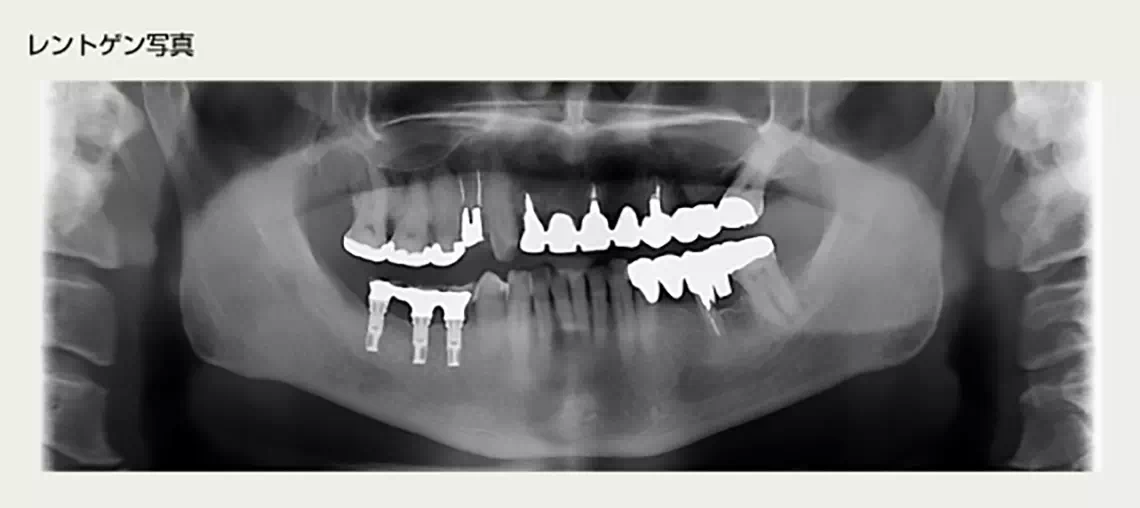

ほとんど歯の無い方 50代 女性

30代より徐々に歯がなくなり入れ歯にしていましたが、発音によっては入れ歯がはずれてしまい困っていました。インプラントで外れない綺麗な歯が欲しいという要望で、上顎にインプラント治療を行うことになりました。